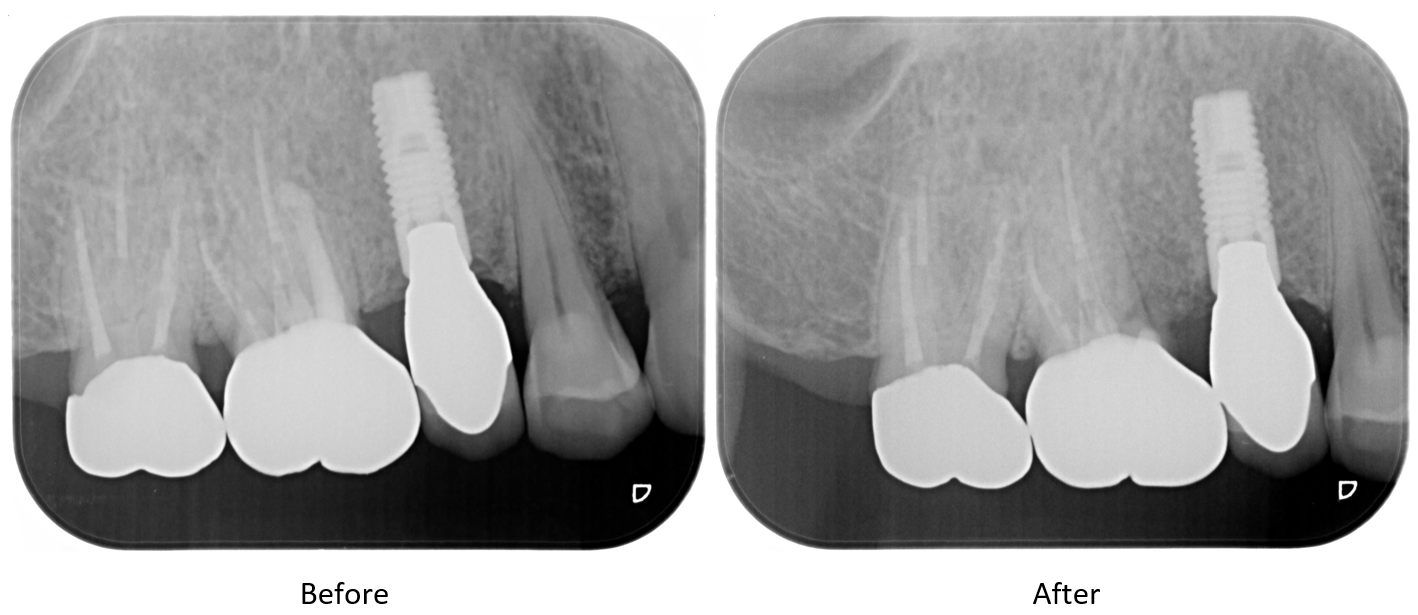

症例2

| 患者様データ | 70代 男性 |

| 来院時の主訴 | 「右上の歯が噛むと痛い。」 |

| 医院の診断 | 近心頬側根の歯根破折 |

| ここがこだわりのポイント!☝ |

右上の奥歯には3つの根っこがあり、そのうちの2つは健康で1つだけが破折していました。破折している歯根のみを切除し抜歯することで、残った歯を保存することができました。 |